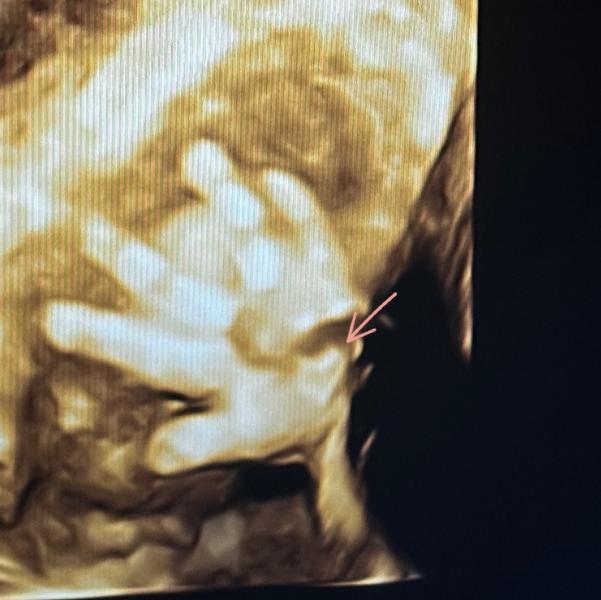

Доченька, это все благодаря твоему появлению в моей жизни! Своими активными пиночками ты даешь мне осознание реальности происходящего. Я люблю тебя больше жизни.